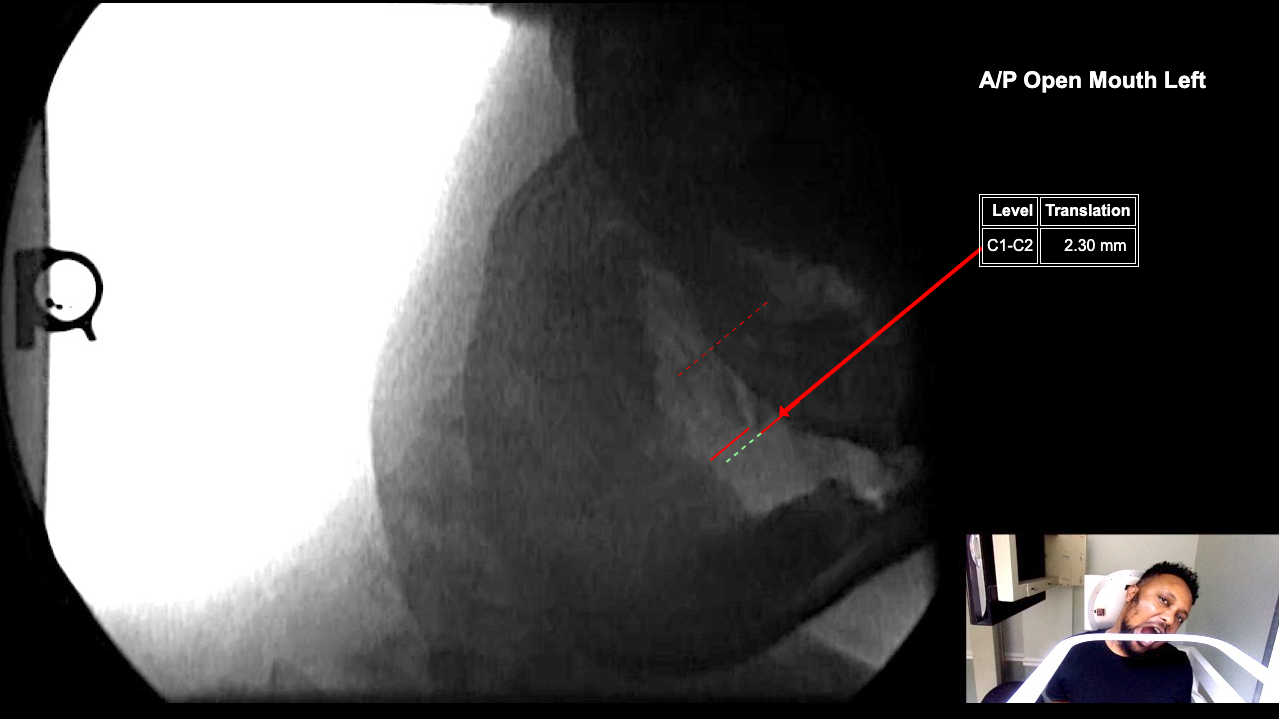

Image 2